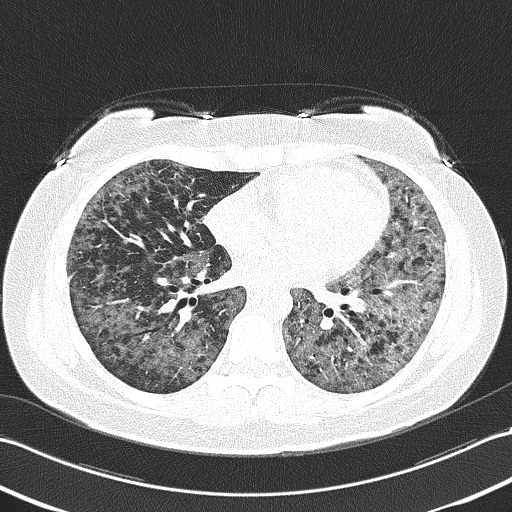

Рентгеновские снимки при пневмоцистной пневмонии